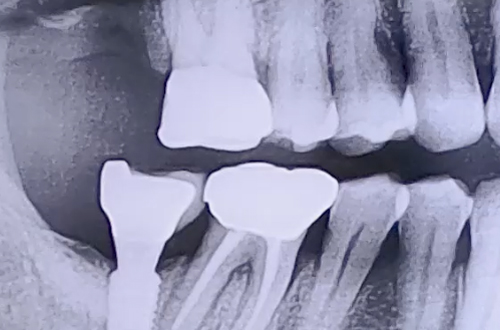

BEFORE

발치를 한 후에 한달 이상 시간이 지났음에도 잇몸이 아물지 않아 임플란트에 앞서 뼈이식을 앞서 계획해 드린 환자분이십니다.

한달 이상 아물지 않은 것을 보면 당시 잇몸 상태가 많이 안 좋고 염증도 심하셨던 것이 아닌가 추정해 볼 수 있습니다. 그 영향으로 임플란트가 들어갈 자리의 잇몸뼈가 거의 없으셨습니다.

이 상태로 임플란트를 식립할 수는 없기 때문에 우선 뼈이식을 통해서 잇몸뼈를 충분히 보강하고 단단해지기까지 기다렸다가 임플란트를 식립하는 지연식립으로 계획하시고, 뼈이식 치료를 우선적으로 진행하신 케이스입니다.